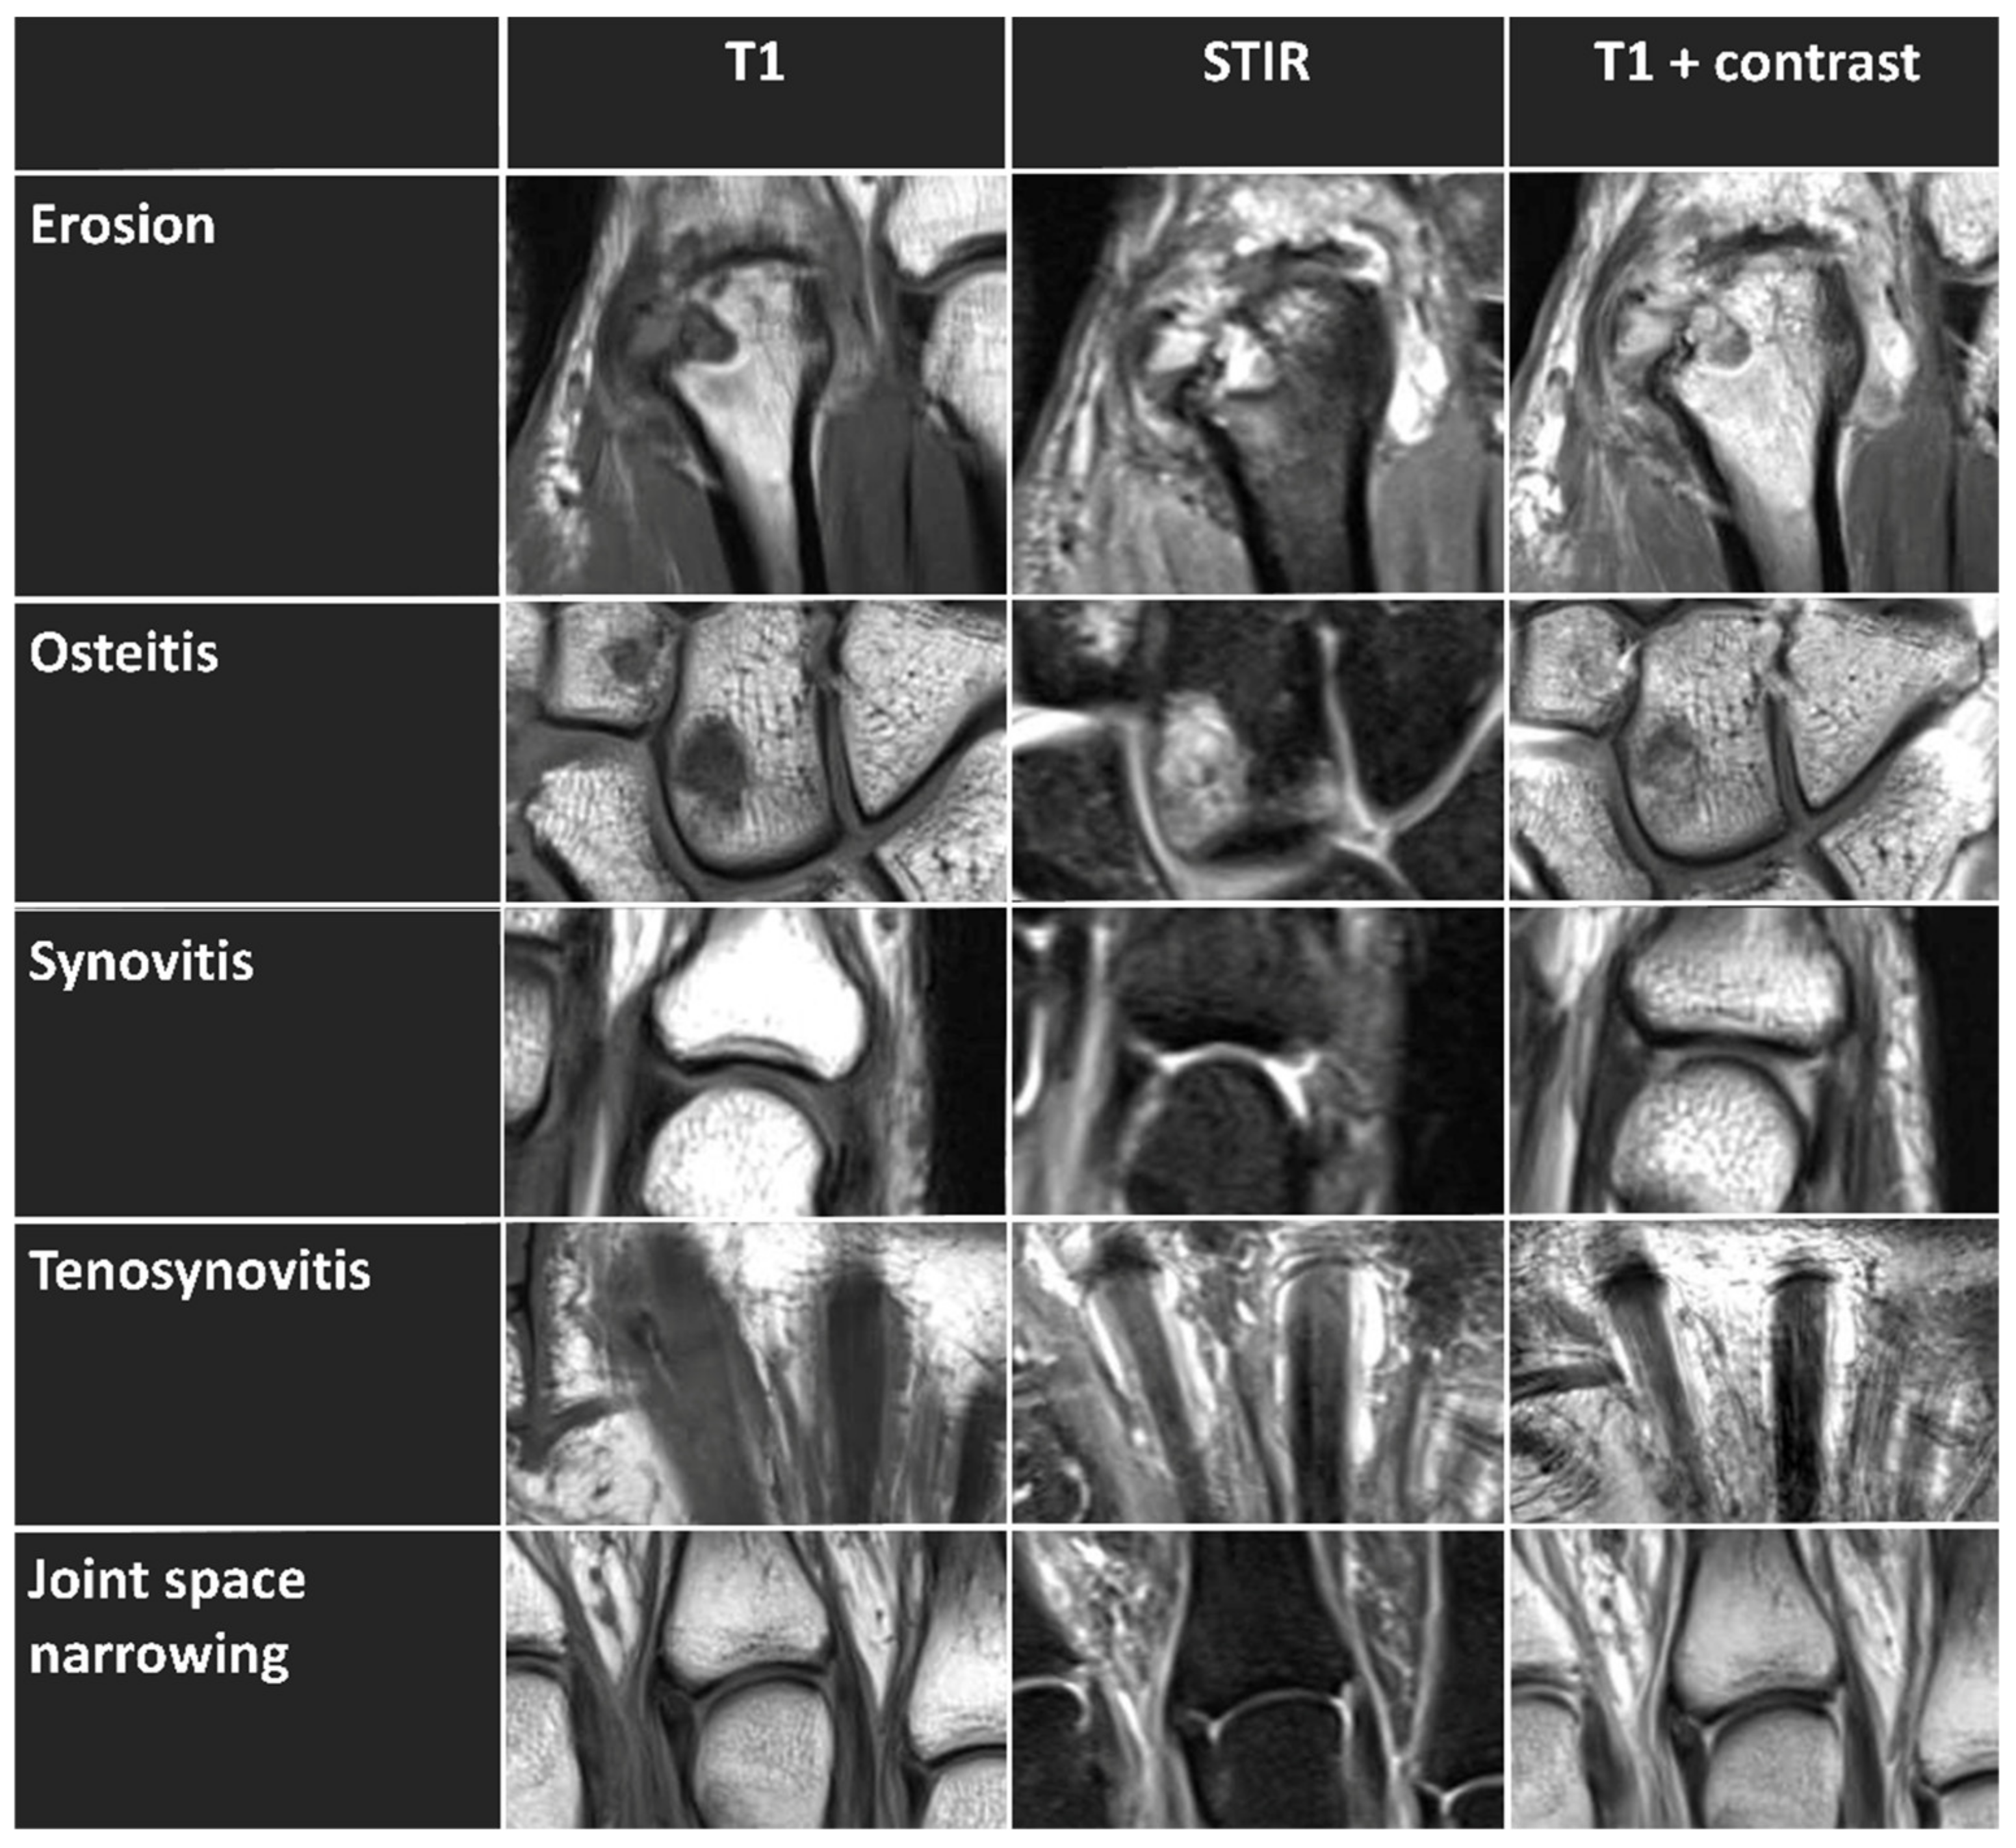

Unilateral MRI studies of the wrist, hand, and MCP joints were performed in the prone position with the hand above the head and the palm facing down (superman position). The clinically more affected hand (n = 25 (right hand), n = 6 (left hand)) was selected to assess the following inflammatory and destructive changes: erosion, osteitis (bone marrow edema), synovitis, tenosynovitis, and JSN (as a sign of cartilage loss). Erosions, osteitis, and JSN were assessed using axial and coronal T1-weighted turbo spin-echo (TSE) and coronal STIR sequences without exogenous contrast enhancement (Figure 1). Semiquantitative assessment of synovitis and tenosynovitis based on RAMRIS was performed using contrast-enhanced coronal T1-weighted TSE sequences without fat suppression and axial T1-weighted spin-echo (SE) sequences with spectral fat saturation (in the following, referred to as “synovitis-contrast” and “tenosynovitis-contrast”). To this end, gadoterate meglumine (Gd-DOTA, Dotarem, Guerbet, Roissy CdG CEDEX, France) was injected intravenously, and a delay of 6 min was chosen until the post-contrast sequences were acquired.

Figure 1. Exemplary imaging features (erosion, osteitis, synovitis, tenosynovitis, and joint space narrowing) that are scored semiquantitatively based on RAMRIS, shown in unenhanced MRT T1-weighted sequence (left column), STIR sequence (middle column), and enhanced T1-weighted postcontrast sequence (right column). Erosion is visualized at the bare area of the distal metacarpal bone of the second digit (i.e., the MCP joint base) of the right hand of a 48-year-old male patient. Osteitis is visualized in the right carpal bones with bone marrow edema in the capitate and trapezoid of a 56-year-old female patient. Synovitis is visualized in the right metacarpophalangeal joint of the fifth digit of a 53-year-old female patient. Tenosynovitis is visualized around the right flexor tendon of the second and third digit of a 75-year-old female patient. In the last row, metacarpophalangeal joints of the right hand with normal joint space without evidence of cartilage loss of a 52-year-old female patient are shown.